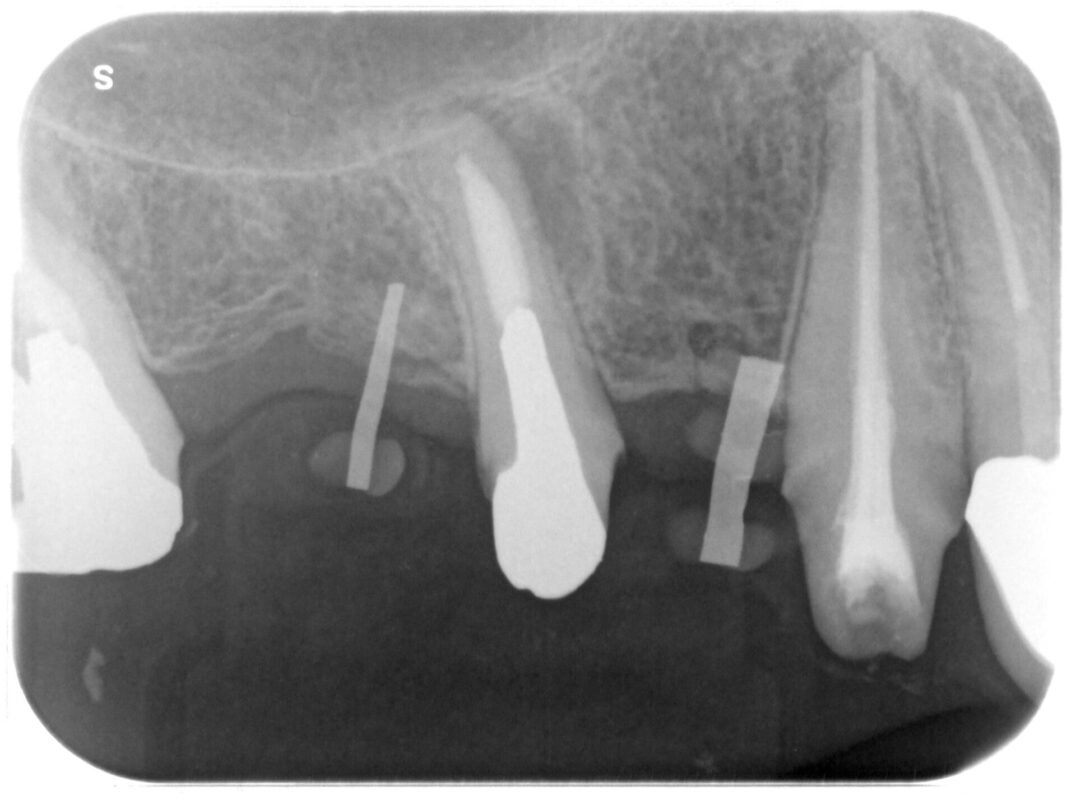

術前

レントゲン写真には歯根先に何やら影が。

1年くらい前に撮影していたものには何も写っていませんでした。

7┛は保存、5┛抜歯、654┛インプラントブリッジ(64┛部にインプラント)、3┛保存という治

療計画です。

6┛部インプラント治療計画しましたが、術前のCT検査で骨の厚みが5mmしかなく、骨の移植が必要と

診断、今回はソケットリフトによる骨移植としました。